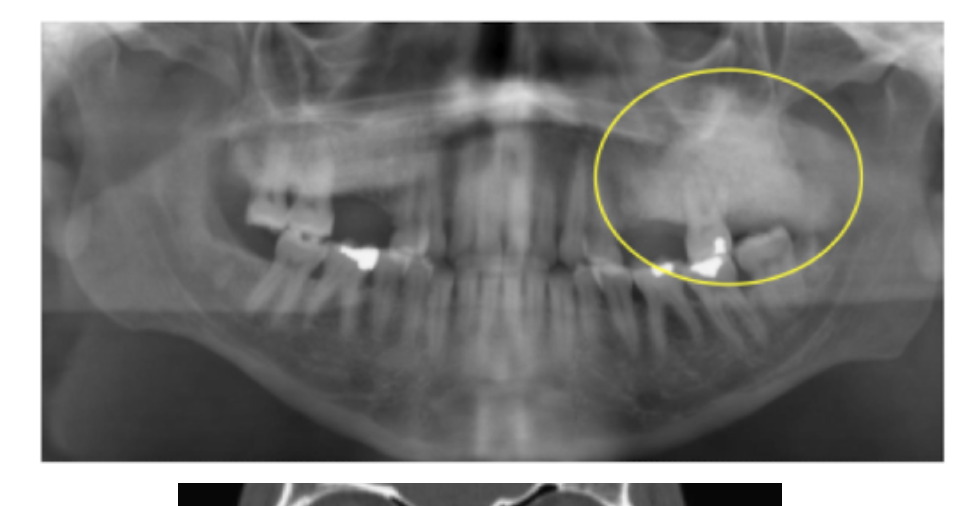

Cherubism

Clinical: Symmetrical Bilateral Swelling

Radiographically:

* expansile bilateral multilocular RL

Stops growing after puberty